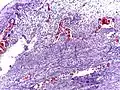

Pathology diagnosis of appendicitis can be made by detecting a neutrophilic infiltrate of the muscularis propria.

Micrograph of appendicitis and periappendicitis. H&E stain.

Micrograph of appendicitis showing neutrophils in the muscularis propria. H&E stain.